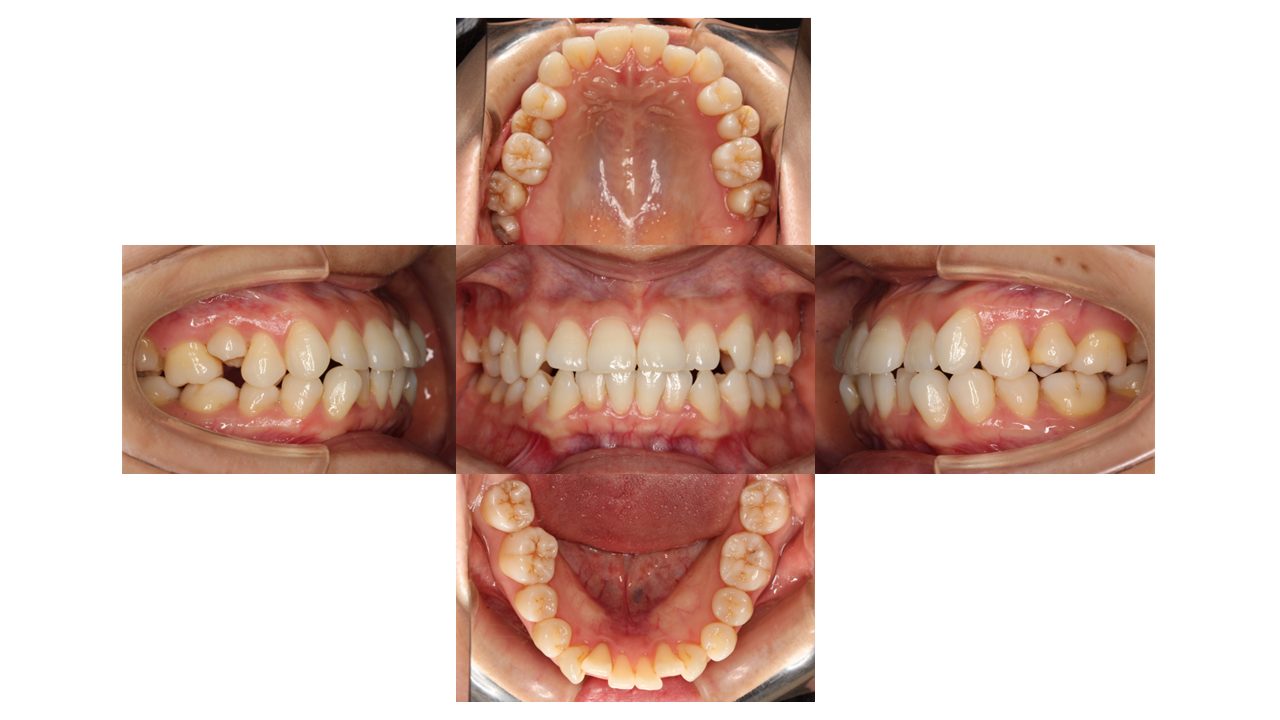

初診時の口腔内の状態です。

上下前歯の凸凹にお悩みでご来院されました。